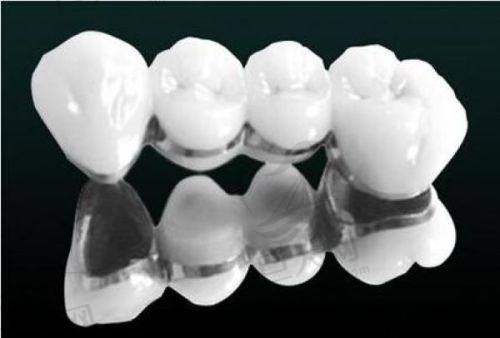

宣城大医口腔医院能为口腔患者完成多种治疗项目,除了上述的特色项目外,还包括口腔种植、儿童口腔、口腔修复等。在儿童口腔方面,医院可以针对儿童不同阶段的口腔问题进行预防和治疗。比如,帮助儿童养成良好的口腔卫生习惯,及时处理乳牙龋齿等问题,为儿童的口腔健康打下坚实的基础。在口腔修复方面,对于牙齿缺失、损坏等问题,医院可以提供多种修复方案,如烤瓷牙、牙贴面等,以修复牙齿的外观和功能。